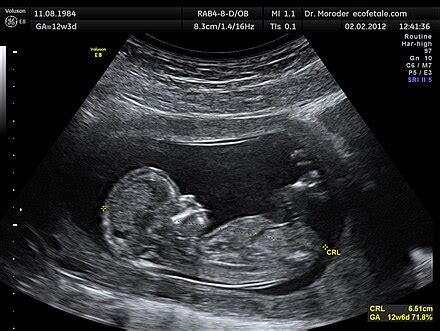

A képalkotó eljárásoknak (pl. ultrahang, MRI) köszönhetően ez a folyamat már a korai időszaktól nyomon követhető, így például a lepény kialakulása is. Tisztában vagyunk vele, hogy már a 8-9 hetes magzat is mozoghat és a végtagok kifejlődésével a 12-13. terhességi hét után a kéz- és lábmozgások is látványosak lehetnek, holott ezek intenzitása még nem éri el azt a szintet, hogy az anyai szervezet ezt jelezze, és az anyában tudatosuljon a mozgások ténye. Első terhesség esetén előfordulhat, hogy a baba mozgása később, a 20-25. hét során válik teljesen felismerhetővé a kismama számára. Második vagy többedik várandósság alatt jellemzően hamarabb felfedezhetővé válnak a megmozdulások.

A fetometria a világ legfontosabb diagnosztikai tesztje. Különleges ultrahangos berendezések használata történik. A modern eszközök lehetővé teszik a magzat képének megszerzését és a teste alapvető paramétereinek tanulmányozását. A vizsgált fő paraméterek a test hossza és a testtömeg. A magzati élet minden egyes időszakában a normál értékük eltérő. Munkájukban az orvosok speciális táblázatot használnak. A terhesség minden hétére jellemző vizsgált paraméterek összes normál értékét tartalmazza.